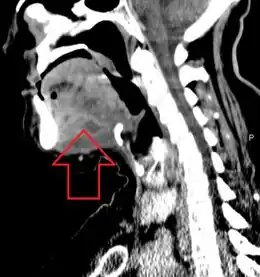

Elevated tongue due to Ludwig's angina -

A CT scan of the neck with contrast material is used to identify deep neck space infections.[19] If there is suspicion of the infection of the chest cavity, a chest scan is sometimes done.[20] Infections originating in the roots of teeth can be identified with a dental X-ray.[21][20]